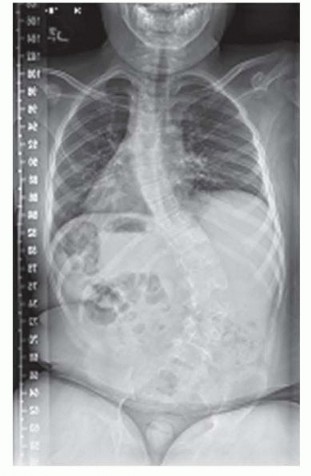

Pelvic Fixation: Better Outcomes for Patients with NMS

Pelvic Fixation for Neuromuscular Scoliosis DEFINITION Neuromuscular scoliosis (NMS) is a spinal deformity in…

Spinal Fusion for Neuromuscular Scoliosis DEFINITION Neuromuscular diseases are heterogeneous between and wit…